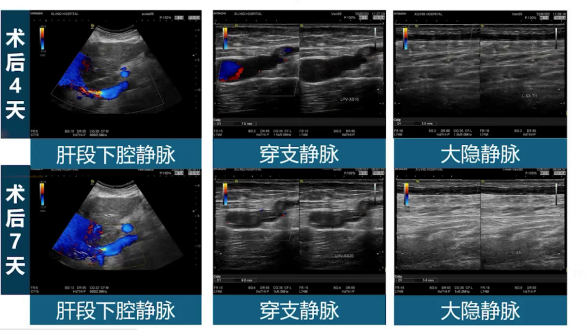

患者术后四天、七天,肝段下腔静脉狭窄解除且维持良好,病理性穿支静脉及功能不全的大隐静脉闭合良好。术后一个月、三个月,肝段下腔静脉狭窄状态持续解除并维持良好,病理性穿支静脉及功能不全的大隐静脉闭合良好且内径逐渐变细。临床体征改善明显,术前迂曲扩张的腹壁浅静脉在术后一月、三月明显减淡变轻,下肢静脉性溃疡在术后一月愈合,术后三月小腿色沉明显变淡。多学科微创协作使患者术后症状显著改善,疾病严重程度评分降低,生活质量得到提升。